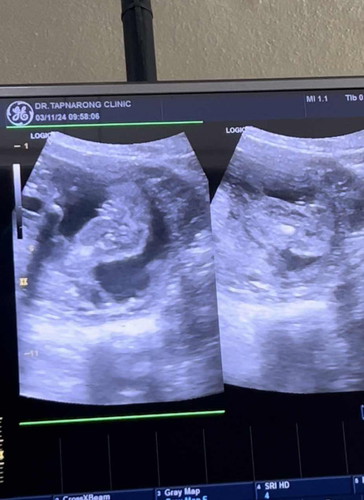

ผู้หญิงหรือผู้ชาย

แม่ๆช่วยดูให้หน่อยค่ะ ว่าหญิงหรือชาย คุณหมอบอกว่าผู้หญิง แต่แม่รู้สึกแปลกๆ คุณหมอพูดเบามากกก😅

ผู้หญิงรึเปล่าคะ